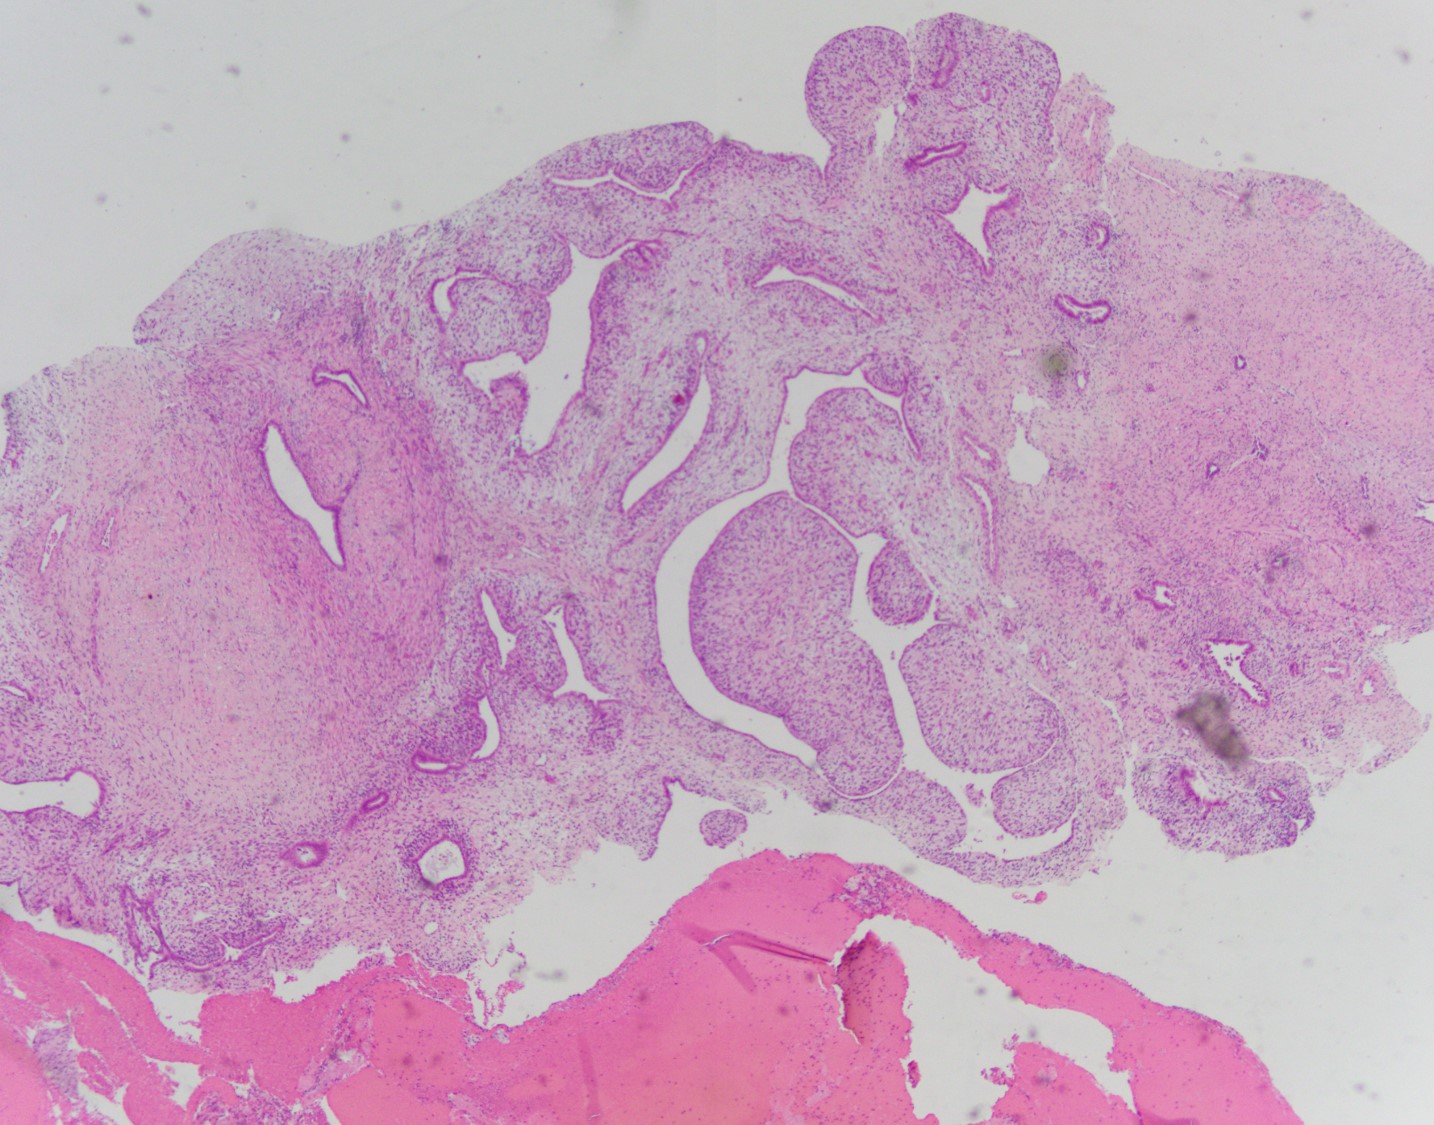

Histologically, MA usually have a phyllodes-type pattern with dilated glands lined by benign endometrial or ciliated epithelium surrounded by a distinct cuff of neoplastic stroma. This stroma is normally hypercellularand can have subtle atypical features. These tumors are often positive for CD10, ER, and PR, however there have been a subset of cases that are negative for CD10.

There are two components comprising this specimen, which are focally intimately associated with one another. The first component consists of endometrial glands and stroma surrounded by smooth muscle bundles, which in the proper clinical setting could represent a benign adenomyomatous polyp. The second component consists of a biphasic process of benign glands and stroma with a phyllodes-like architecture. The stroma surrounding the glands shows periglandular "cuffing" with very low-grade atypia. There is increased mitotic activity (greater than 2 mitoses/10 HPF) in the areas with the phyllodes-like architecture. Immunohistochemical staining showed two distinct staining patterns in the two components. The adenomyomatous polyp component showed CD10 highlighting endometrial stroma in the adenomyomatous areas with surrounding smooth muscle bundles positive for caldesmon and desmin while the stroma in the phyllodes-like area was positive for desmin and caldesmon but was negative for CD10. The patient was treated with a hysterectomy, where there was minimal focal residual disease identified.